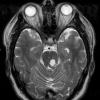

VASCULAR

Cavernous Angioma (9)